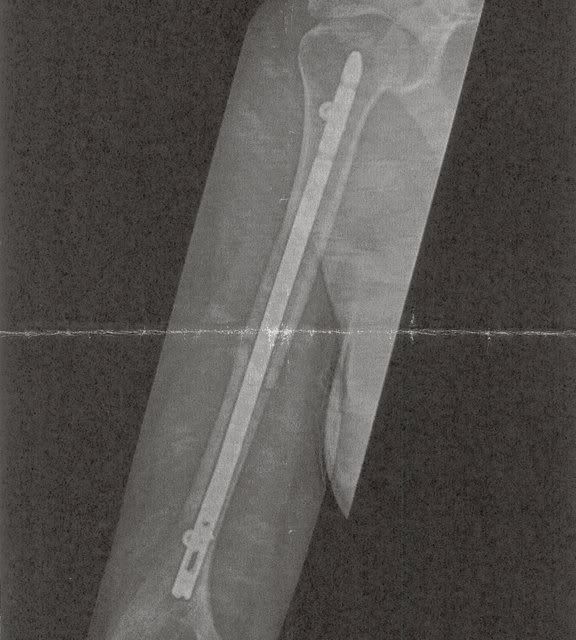

Na 3 uur op de eerste hulp te hebben gezeten mochten we eindelijk zo'n kamertje in, de dokter ging voelen en zei dat hij dacht aan een spierenkwestie maar helaas, na het zien van de foto kwam hij nogal gehaast terug en zei dat hij slecht nieuws had.

Mijn schouder is gebroken, net onder de schouderkop, volgens hem werd dit een vreselijk zwaar en pijnlijk proces.

Vandaag te horen gekregen dat ik niet geopereerd hoef te worden, volgende week dinsdag moet ik terugkomen voor foto's.